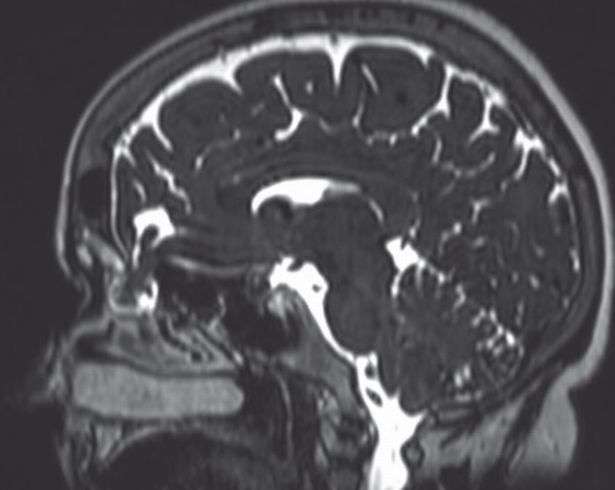

CT Scan mengidentifikasi sebuah struktur seperti kantung berukuran 1,8 cm yang menonjol ke dalam rongga hidung di antara kerusakan pada tulang.

Kantung itu merupakan ensefalokel, sebuah kondisi yang biasanya diidentifikasi pada bayi di mana tulang tengkorak tidak menyatu sepenuhnya, menciptakan celah di mana cairan serebral dan jaringan otak dapat berkumpul di benjolan yang menonjol.

Dokter meyakini tes swab yang dilakukan oleh wanita ini merusak massa di dalam rongga hidungnya yang akhirnya menyebabkan kebocoran cairan serebrospinal.

Cairan serebrospinal adalah cairan bening yang ditemukan di sekitar otak dan sumsum tulang belakang.

Namun masalah sebenarnya adalah kerusakan pada tengkoraknya yang tidak terdiagnosis selama bertahun-tahun. Segera setelah masakah sebenarnya dapat diidentifikasi, dokter mengoperasi untuk mengurangi massa.

Untuk menutup lubang di tulang yang memungkinkan terbentuknya benjolan seperti kantung, mereka menggunakan cangkok kulit jaringan lunak, yang berfungsi sebagai perancah sel untuk memasukkan cangkok ke dalam tulang.

“ Pasien ini memiliki gangguan dasar tengkorak yang tidak terdiagnosis di fovea ethmoidalis yang ada pada pencitraan sejak tahun 2017. Oleh karena itu kami berteori bahwa tes swab itu sendiri sebenarnya tidak berpengaruh pada dasar tulang tengkorak, tetapi tes invasive menyebabkan trauma pada ensefalokel pasien yang sudah ada sebelumnya.”